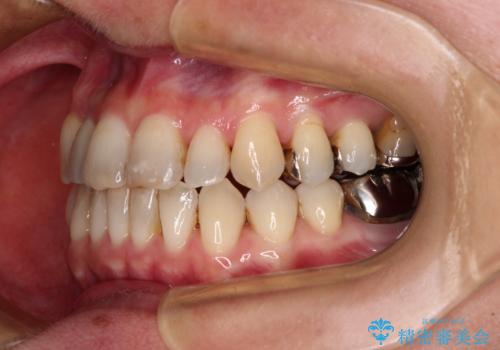

- 前歯の反対咬合を気にして来院された患者様です。

上顎骨の幅が下顎骨よりも小さいので、拡大装置により骨幅を広げて上下関係を改善すると同時にワイヤー矯正で反対咬合の改善を図り、その後インビザラインにて歯並びを整えることとしました。

上顎前歯の矮小歯は矯正治療の途中でオールセラミッククラウンを装着し、左右のバランスを整えることとしました。

急速拡大装置の使用により奥歯の咬み合わせが劇的に変わり、その変化を利用して反対咬合を改善することができました。

治療期間中は奥歯が咬み合わず、食事が取りにくいなどの不都合がありましたが、最終的にはきれいに整えることができました。